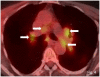

Ipilimumab is a promising novel immunotherapy agent and is associated with a variety of immune-related adverse events (irAE). The purpose of this study was to investigate the manifestations of irAEs on body imaging in patients with advanced melanoma treated with ipilimumab. One-hundred forty-seven patients with advanced melanoma (59 women, 88 men; median age, 64.5 years) treated with ipilimumab were studied. All patients had the baseline and at least one follow-up chest/abdomen/pelvis CT or PET/CT during therapy, which were reviewed by a consensus of two radiologists blinded to the clinical data. Findings indicative of individual types of irAEs were assessed, including thyroiditis, sarcoid-like lymphadenopathy, pneumonitis, hepatitis, pancreatitis, and colitis. Among the 147 patients, 46 (31%) had radiologically identified irAEs. The time interval from the initiation of therapy to the development of irAEs was less than 3 months in 76% (35 of 46) of the patients (range, 0.2-9.1 months). Clinical characteristics did not differ between patients with and without irAEs (P > 0.18). Among the individual types of irAEs, colitis was most common (n = 28; 19%), followed by sarcoid-like lymphadenopathy (n = 8; 5%) and pneumonitis (n = 8; 5%). Hepatitis (n = 3), thyroiditis (n = 2), and pancreatitis (n = 1) were less common. The resolution of irAEs was noted in 32 of 36 patients (89%) with further follow-up scans, with a median time of 2.3 months after the detection of irAE. In conclusion, irAEs were noted on body imaging in 31% of patients with melanoma treated with ipilimumab. Colitis was the most common, followed by sarcoid-like lymphadenopathy and pneumonitis. The results call for an increased awareness of irAEs, given the expanding role of cancer immunotherapy.